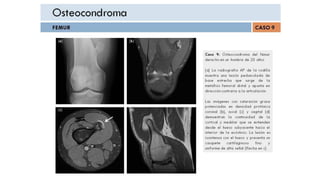

OSTEOCONDROMA

Osteocondroma .- Consideraciones Generales

•El osteocondroma es el tumor óseo benigno más común y la neoplasia

esquelética más común

o Representan aproximadamente el 35% de todos los tumores óseos benignos

y el 9% de todos los tumores óseos

•Son proyecciones óseas cubiertas de cartílago de la superficie externa de un

hueso

•Se encuentran con mayor frecuencia alrededor de la rodilla (40%) y del hombro,

aunque pueden aparecer en cualquier hueso.

•Casi todos se diagnostican en pacientes menores de 20 años con un marcado

predominio masculino: femenino (3: 1)

•Crecen hasta la madurez esquelética y luego dejan de crecer cuando se fusiona

la placa epifisaria, Los osteocondromas tienden a aparecer cerca de una placa de

crecimiento epifisario y se alejan de la fisis

OSTEOCONDROMATOSIS

MÚLTIPLE EN NIÑA DE

13A.